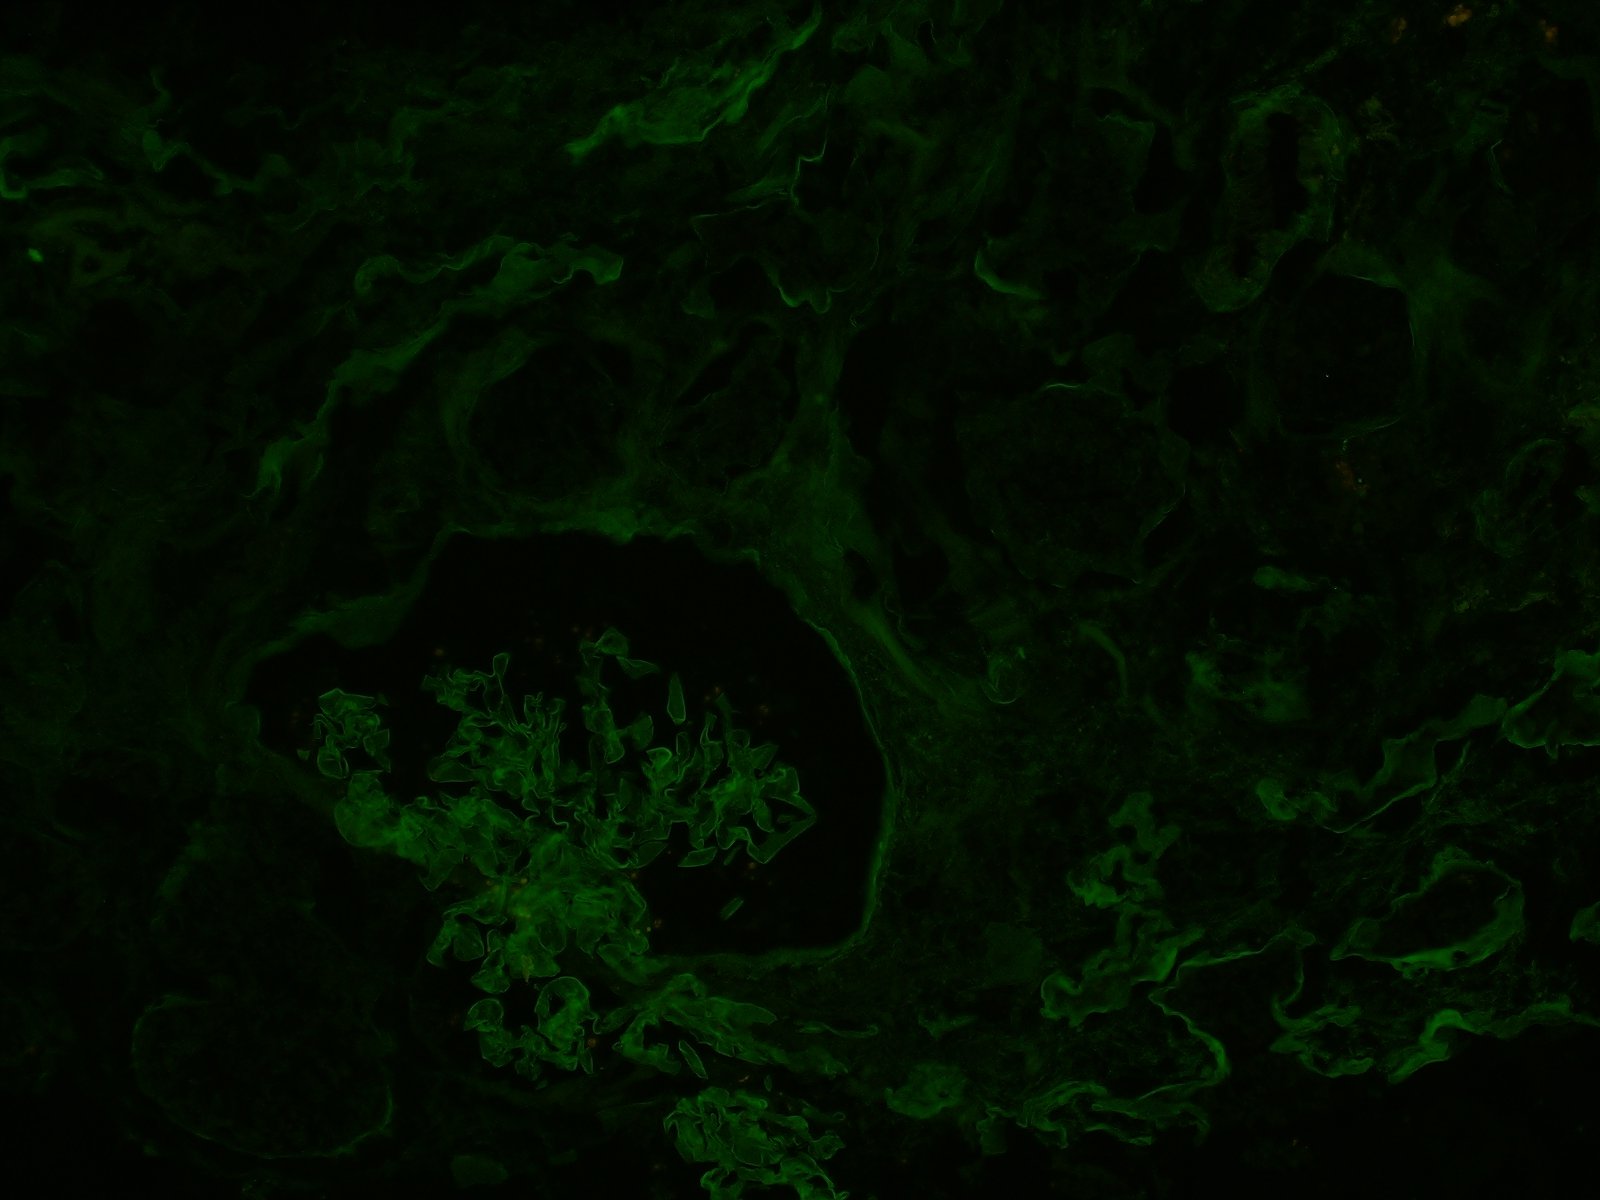

Immunofluorescence (IF): Fluorescent-labeled antibodies are used to identify the antigens: primarily, the immunoglobulins IgG, IgM, and IgA, complement components (C3, C1q, and C4), fibrin, and kappa and lambda light chain. Additional antibodies can be used if needed. See the difference between a negative (left) and positive (right) IF stain below.